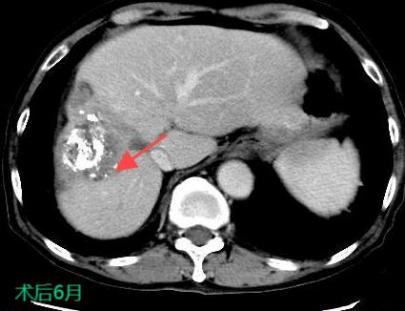

TACE/HAIC:經(jīng)肝動(dòng)脈灌注化療栓塞(TACE)、肝動(dòng)脈內(nèi)灌注化療藥物(HAIC)是在不開(kāi)刀暴露腫瘤病灶的情況下,在皮膚上做直徑幾毫米的切口,在影像設(shè)備的引導(dǎo)下,導(dǎo)絲和導(dǎo)管插入肝臟腫瘤血管,注入栓塞劑和化療藥物使肝臟腫瘤內(nèi)化療藥物濃度提高,并減少全身的藥物總濃度,達(dá)到提高化療效果并減少毒副作用的目的。對(duì)于無(wú)法手術(shù)切除的巨塊型肝癌、肝內(nèi)多發(fā)肝癌病灶、肝癌結(jié)節(jié)破裂出血有良好的治療效果。

b17ea7a367aa45238a40cb018e649a85.Jpeg

30b6dc2c583d47819f8420b9ddcf6480.Jpega4406a7ea8e948c58d57bbae15214f34.Jpeg

射頻熱消融被廣泛地用于原發(fā)性肝癌的治療,將電極針插入腫瘤通過(guò)射頻能量使病灶局部組織產(chǎn)生高溫,凝固腫瘤,近似于外科手術(shù)根治性切除的效果。

射頻熱消融治療